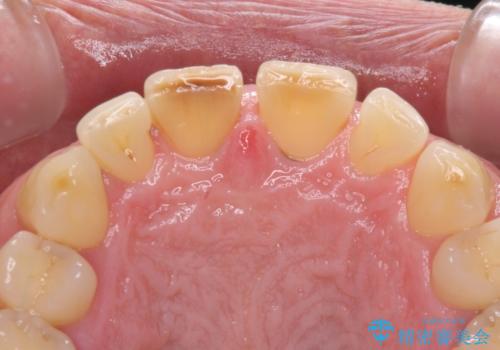

- 前歯の目立つ隙間を気にして来院された患者様です。

高校生の頃に矯正治療を行ったものの、強い咬合力により上顎が拡大され、正中に隙間ができてしまいました。

通常では歯の周囲全体を削った上でクラウンを装着することが多いのですが、咬合力が非常に強く、クラウンではセラミックが欠けてしまう可能性が考えられたため、咬合を変えることとのないラミネートベニアにて治療を行うこととしました。